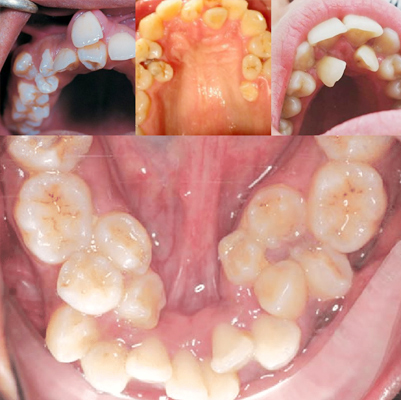

Hyperdontia is a dental condition in which a person develops extra teeth in the mouth beyond the normal number. These additional teeth are called supernumerary teeth.

They can appear in the dental arches (the curved areas where teeth attach to the jaw).

• Humans normally develop 20 primary (baby/deciduous) teeth and later 32 permanent (adult) teeth.

• In hyperdontia, there may be extra primary or permanent teeth.

• Extra primary teeth are less common, while extra permanent teeth are more frequently seen in adults.

• Can occur in both the upper and lower jaw, though most often seen in the upper front teeth region (mesiodens).

• Mesiodens – between two upper front teeth.

• Paramolar – near molars.

• Distomolar – behind molars (sometimes called “fourth molar”).

If untreated, extra teeth can cause:

• Crowding of teeth

• Misalignment or shifting of normal teeth

• Delayed eruption of permanent teeth

• Gaps or spacing problems

• Difficulty chewing or speaking

• Jaw pain or discomfort

• Increased risk of cysts, infections, or gum issues